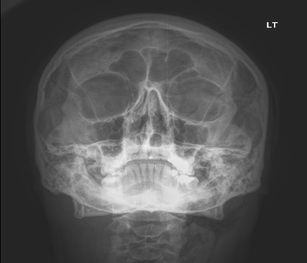

A 40-year-old man developed a swelling to his left side of his face during the course of a root canal treatment. He was undergoing some dental restoration of his left upper second molar. During the cavity preparation, the dentist noticed some swelling over the left parotid area that slowly started to spread to the left cheek and lower eyelid. The root canal treatment was stopped, and the patient was referred to our emergency department as an allergic reaction/anaphylactic reaction by his dentist in an ambulance. Examination revealed a swollen left half of his face (Fig. 1) with crepitus on palpation. There was no trismus. There was no increase in the size of the swelling during his stay in the department. There was no dysphagia. The vital signs were normal, and he was apyrexial. The cardiovascular and respiratory system examination was normal. The sudden onset of head and neck swelling after a dental procedure made us draw up a list of differential diagnoses that included haematoma, cellulitis, allergic reaction, angioedema and subcutaneous emphysema. However, we managed to exclude the others one by one on clinical examination, haematological, biochemical and radiological investigation. Haematoma was unlikely as there was no active bleeding during the procedure or after the procedure. There was no tenderness on palpation, no visible haematoma on intra- or extra-oral examination, no history of clotting abnormalities, and his clotting studies were normal. Cellulitis was unlikely as there were no local signs of inflammation such as warmth, redness, tenderness or raised temperature. The white cell count and the C-reactive protein were normal as well. The swelling was localised to the left half of the face and neck with no other rash or swelling elsewhere. The patient was not known to be allergic to any substances and had undergone previous root canal procedures under the same dentist. This ruled out an allergic reaction. Furthermore, intraoral examination did not reveal any swelling to the tongue or the uvula or lips, etc. There was no family history of allergy or angioedema. He was not on any medications that could have caused angioedema. Furthermore, angioedema swelling does not produce palpable crepitus. This ruled out an angioedema. There was palpable crepitus felt over the swelling on clinical examination. Given that an air turbine dentist drill was used, a diagnosis of subcutaneous cervico-facial emphysema was made. The subcutaneous emphysema was confirmed on facial x-rays (Fig. 2). A chest x-ray was also performed to rule out the presence of a pneumomediastinum (Fig. 3). The patient was admitted to our Clinical Observation Unit and was provided with high-flow supplemental oxygen via a reservoir bag. He was also treated with antibiotics (Co-Amoxiclav 625 mg three times a day for 7 days). No antihistamines, adrenaline or corticosteroids were used in his management. The patient made an uneventful recovery, his facial swelling subsided, and he was discharged home around 14 h after his initial presentation to the Emergency Department.